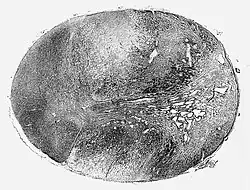

![]() Glioblastoma arising in an astrocytoma. This spinal cord exhibits both a lightly staining microcystic astrocytoma as well as a darkly staining glioblastoma.  | |